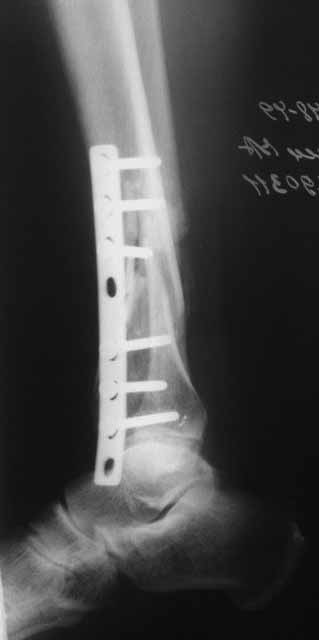

Коллеги!

Место ложного сустава не выглядит гипертрофическим. Нет разрастания костной мозоли.

Закрыто все сделать не удасться. Фрагмент стержня нужно удалить, придется трепанировать кортикал и удалять фрагмент конец стежня. Свободная костная пластика - высой риск нагноения. Как вы думаете, может микрохирургически заместить дефект трансплантом из малоберцовой кости на сосудистой ножке это выход? В приложении статья о замещении костных дефектов трансплантатми на сосудистой ножке. описывают васкуляризованную костную пластику при ложных суставах.